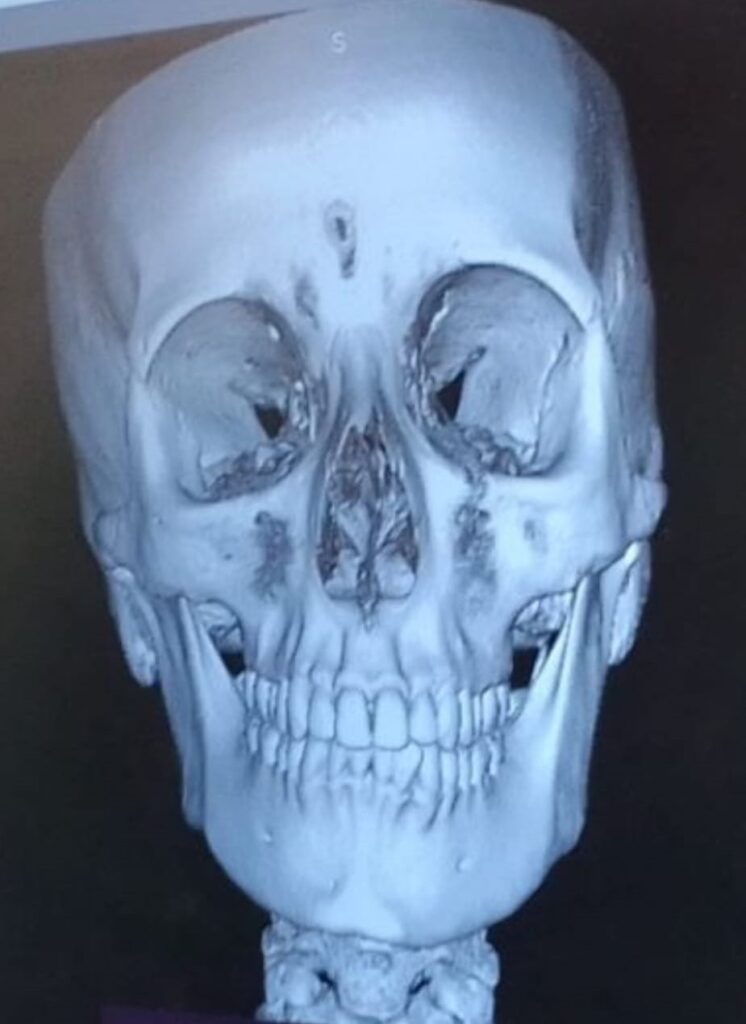

Questa ragazza invece ha un grado di Dis-Equilibrio più evidente e l’evidenza del confronto prima e dopo è palese:

A livello di rx possiamo dire che cranio e mandibola, prima e dopo, sono diventati simmetrici applicando la scoperta del Meccanismo OG. Un evento esclusivo mai visto in tutto il mondo accademico e non, in tutto il pianeta.

I condili della mandibola si riallineano, si riallineano le ossa SUI TRE PIANI SPAZIALI ruotando tra loro e inclinandosi fino ad arrivare ad una posizione di simmetria e di EQUILIBRIO MECCANICO ABITUALE.

Per la rx a destra abbiamo ricevuto complimenti anche da una prestigiosa università italiana che è tra le più prestigiose del mondo.